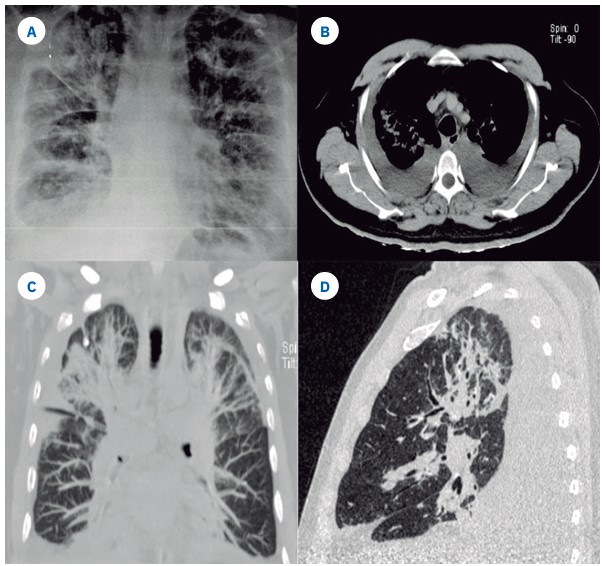

La tomografía de tórax mostró neumonía con patrón mixto, asociada con derrame pleural, atelectasias bilaterales y adenopatías mediastinales (Figura 1). La biometría hemática reportó eosinófilos 3650 células/mL, e IgE sérica para Aspergillus Fumigatus, con un valor de 0.84 UI/mL. Se inició tratamiento con itraconazol (200 mg/12 h) y prednisona (40 mg/día), con lo que se observó disminución del requerimiento de oxígeno e infiltrados pulmonares. Se decidió darlo de al, con seguimiento a los tres meses. Las pruebas de función respiratoria informaron: capacidad vital forzada (FVC): 48.6%, volumen espirado máximo en el primer segundo de la espiración forzada (FEV1): 40.3% y FEV1/FVC: 83.3, por lo que requirió rehabilitación pulmonar y tratamiento a base de broncodilatadores.

Figura 1 Figura 1. A) Radiografía de tórax que muestra infiltrados reticulares bilaterales, que confluyen en las bases pulmonares. B, C, D) Tomografía de tórax que evidencia engrosamiento intersticial peribroncovascular, bilateral, asimétrico en ambos lóbulos superiores, con bandas de atelectasia y derrame pleural bilateral que provoca colapso pulmonar de los segmentos basales.